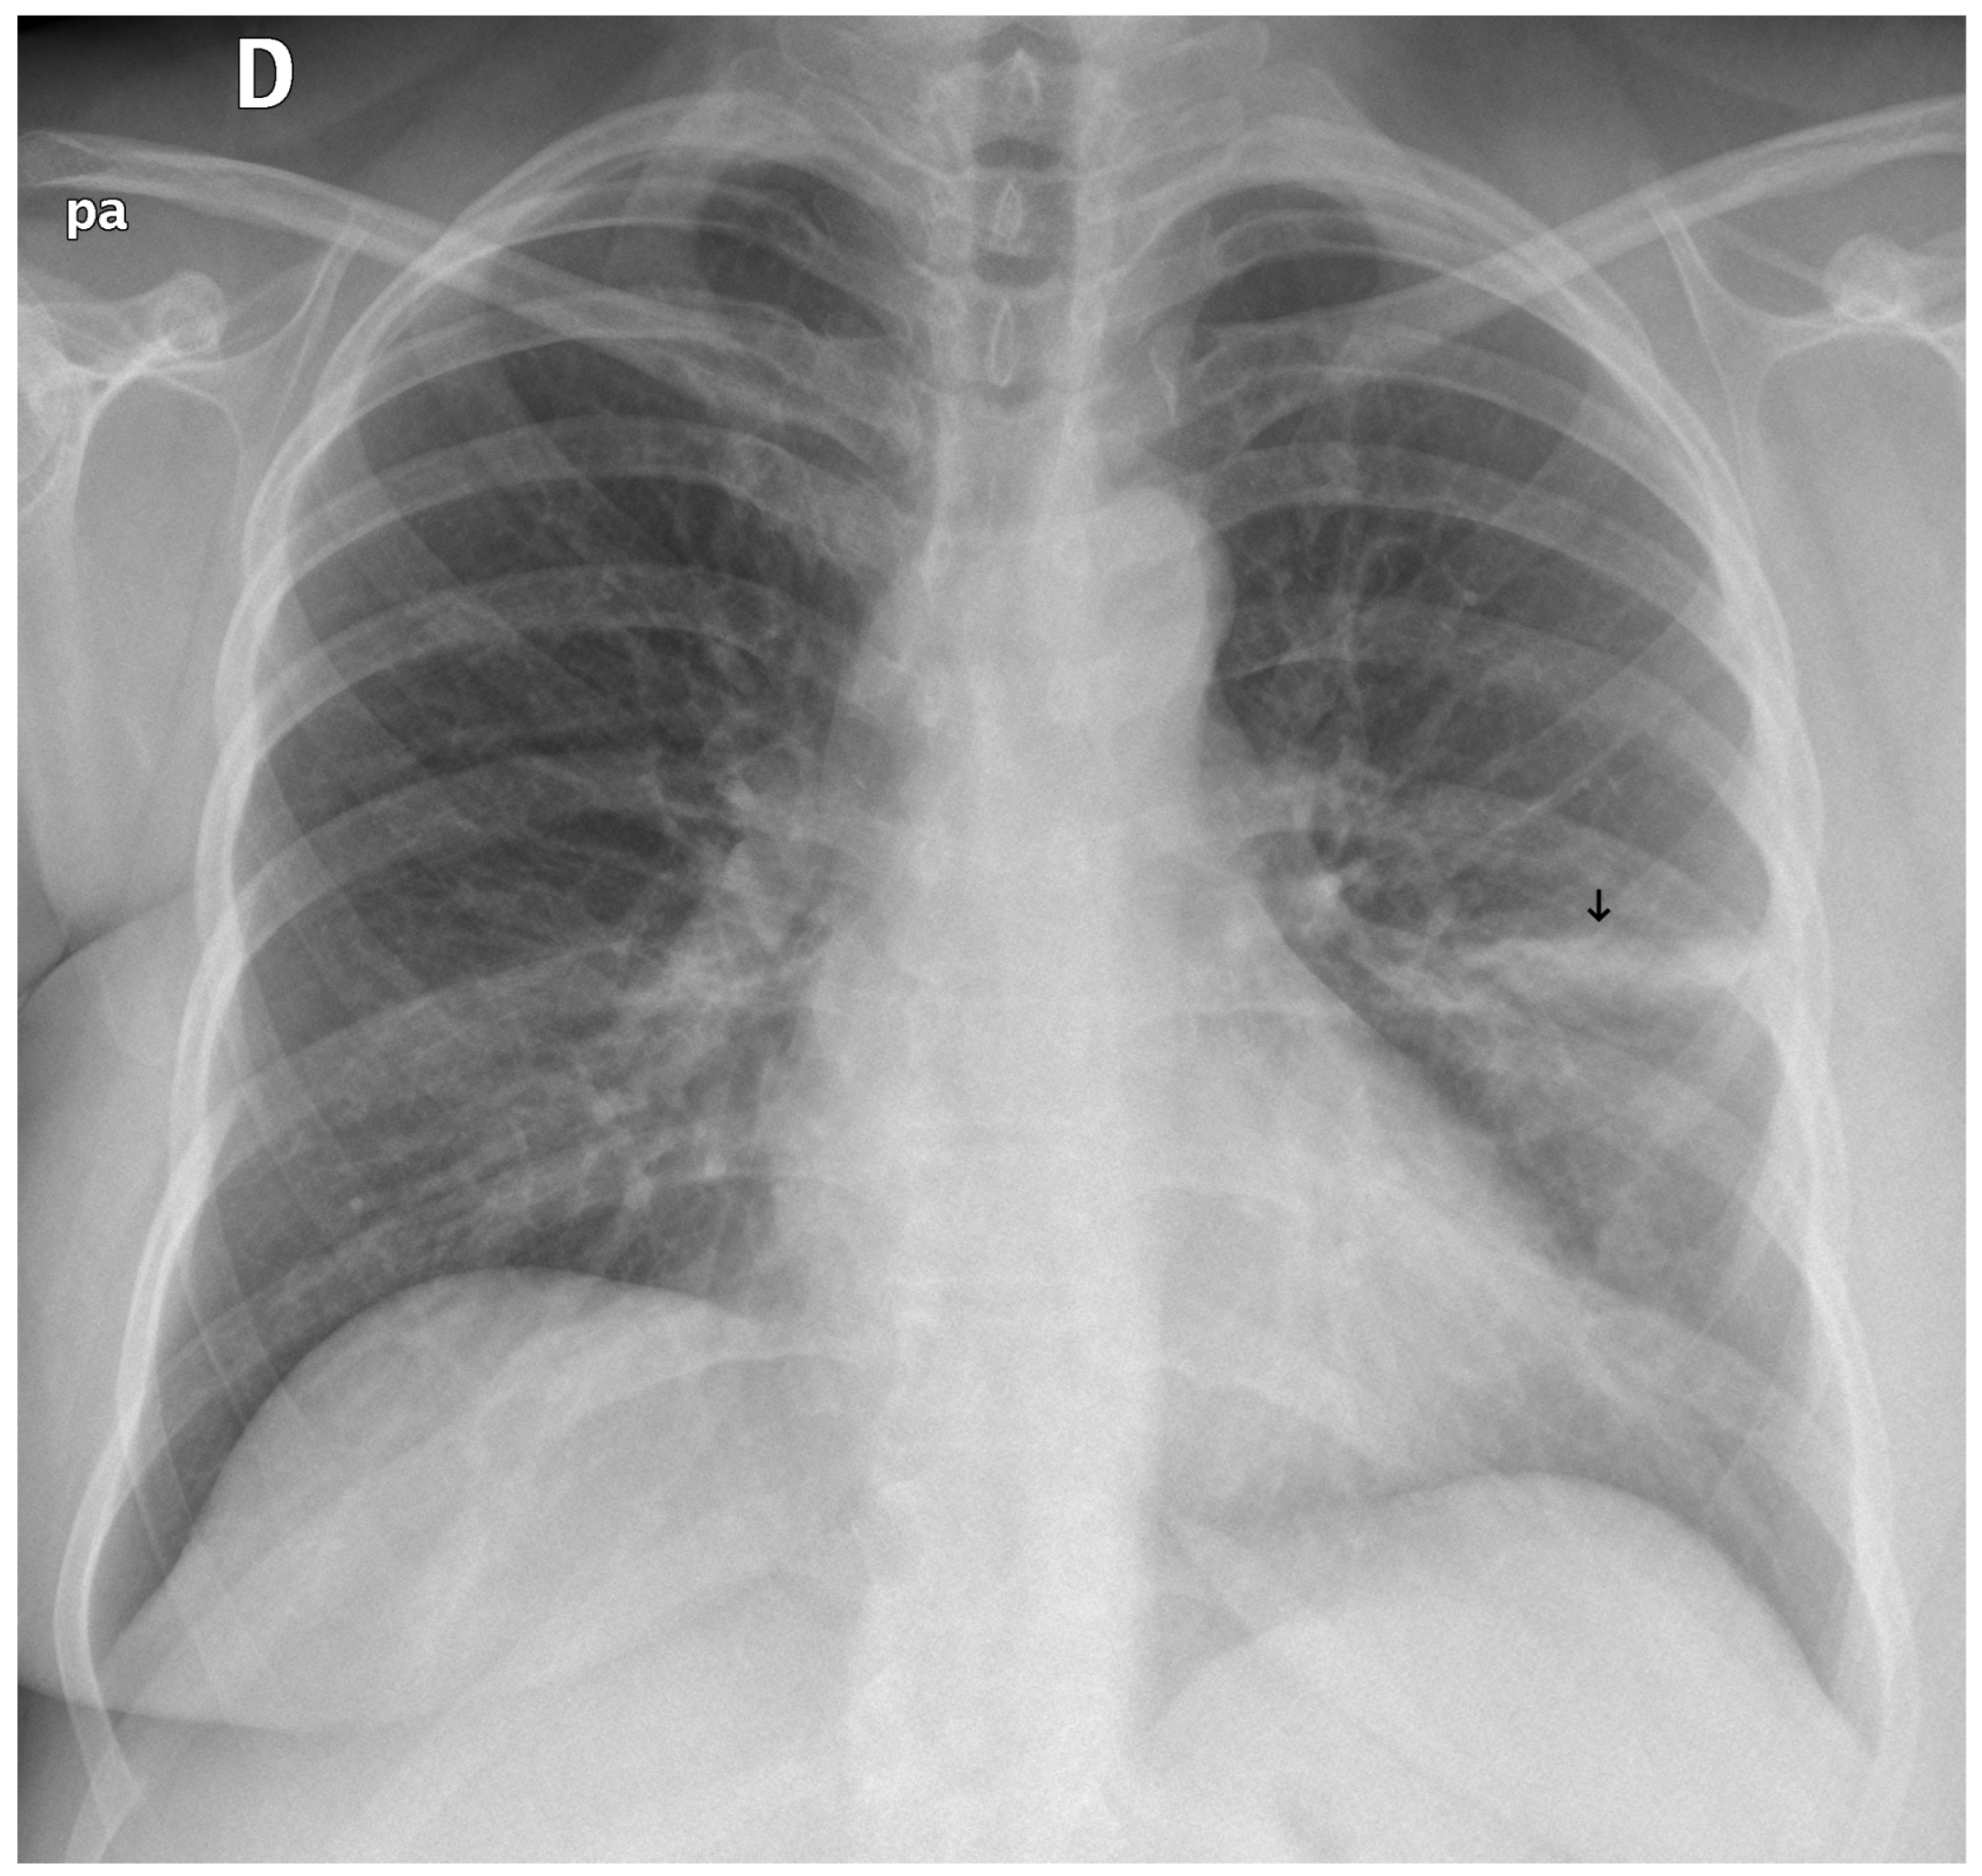

Figure 4. A true positive example of a nodule/mass (left) and its bounding box generated image (right). In this case, the report indicated opacity; however, the algorithm classified as a mass.

3.3. Error Analysis

An analysis of the algorithm’s false negatives revealed a nuanced performance profile, where a specific miss did not always equate to a complete system failure. Across the board, a substantial number of cases with a false negative for a particular pathology were nevertheless correctly identified as abnormal by the general “yes-finding” classifier or had other co-occurring true positive pathologies. For example, out of 38 false negatives for opacity, the algorithm correctly identified the exam as abnormal in 25 cases. In many instances of a missed finding, the algorithm successfully detected other pathologies within the same study. Misclassification was another notable source of error, where an existing pathology was detected but incorrectly labeled, such as opacities being predicted as masses or nodules (Figure 4). Radiologist review of these false-negative cases frequently noted findings that were “subtle,” “small,” “doubtful,” “seen on lateral image only,” or “non-specific.” In other cases, the algorithm correctly identified a more critical finding, like a large pleural effusion, while missing a secondary, less significant pathology (Figure 3). Figure 9, Figure 10 and Figure 11 illustrate false negative cases for opacity, pneumothorax, and nodule, respectively. This highlights the inherent limitations and inevitable failures of this kind of system.